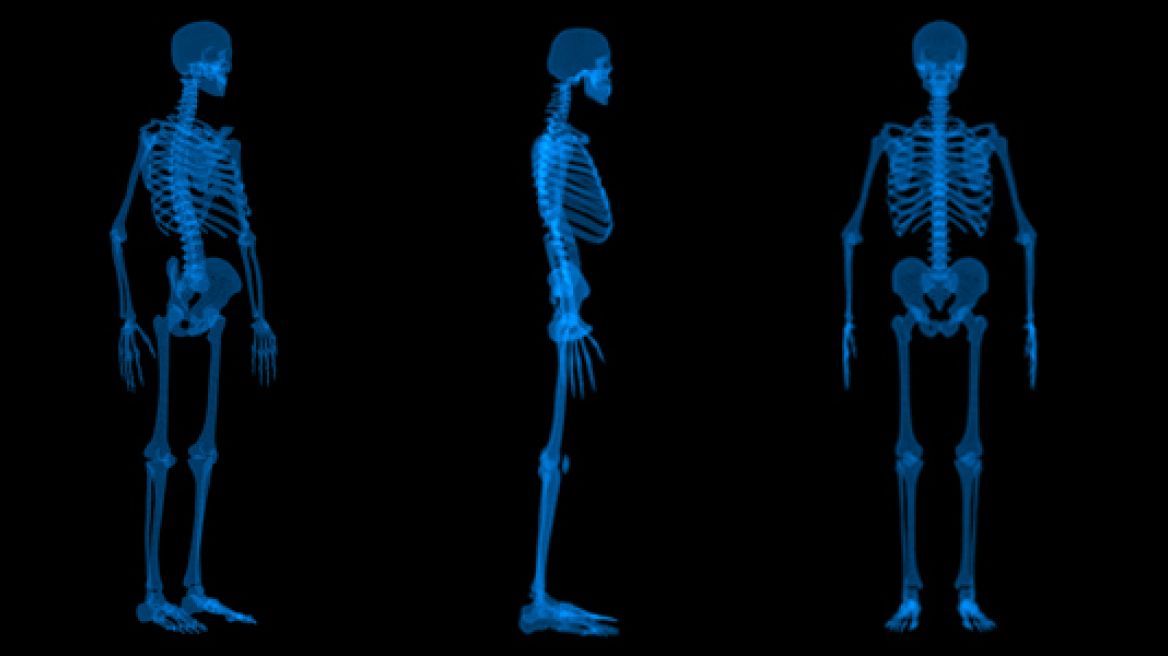

Κι όμως, σήμερα αφορά στην Ελλάδα περισσότερες από 500.000 γυναίκες, αλλά και 1 στους 5 άντρες άνω των 50 ετών, από τους οποίους 75% δεν το γνωρίζει καν. Η οστεοπόρωση είναι η πιο συχνή πάθηση των οστών και χαρακτηρίζεται από χαμηλή οστική πυκνότητα και αλλοίωση της δομής των οστών, με συνέπεια τη μείωση της αντοχής τους και τον αυξημένο κίνδυνο κατάγματος.

Είναι εντυπωσιακό ότι παρά την συχνότητα και την σοβαρότητα της νόσου, το 93% των ανδρών και το 58% των γυναικών δεν έχουν κάνει ποτέ μέτρηση οστικής πυκνότητας! Έτσι, η διάγνωση της οστεοπόρωσης γίνεται συχνά μετά από την εμφάνιση ενός σχετιζόμενου κατάγματος, παρότι οι πάσχοντες μπορεί να εμφανίζουν συμπτώματα όπως πόνο στα οστά, αστάθεια, απώλεια ύψους, αλλά και τη χαρακτηριστική «καμπούρα».

Η εμφάνιση της οστεοπόρωσης οφείλεται σε παράγοντες όπως η εμμηνόπαυση, η κληρονομική προδιάθεση, ορμονικές διαταραχές όπως εκείνες του θυρεοειδούς, η λήψη φαρμάκων (κορτιζονούχα, αντιπηκτικά κ.ά.), οι χημειοθεραπείες, το χαμηλό σωματικό βάρος, η έλλειψη ασβεστίου και βιταμίνης D, αλλά και ο καθιστικός τρόπος ζωής.